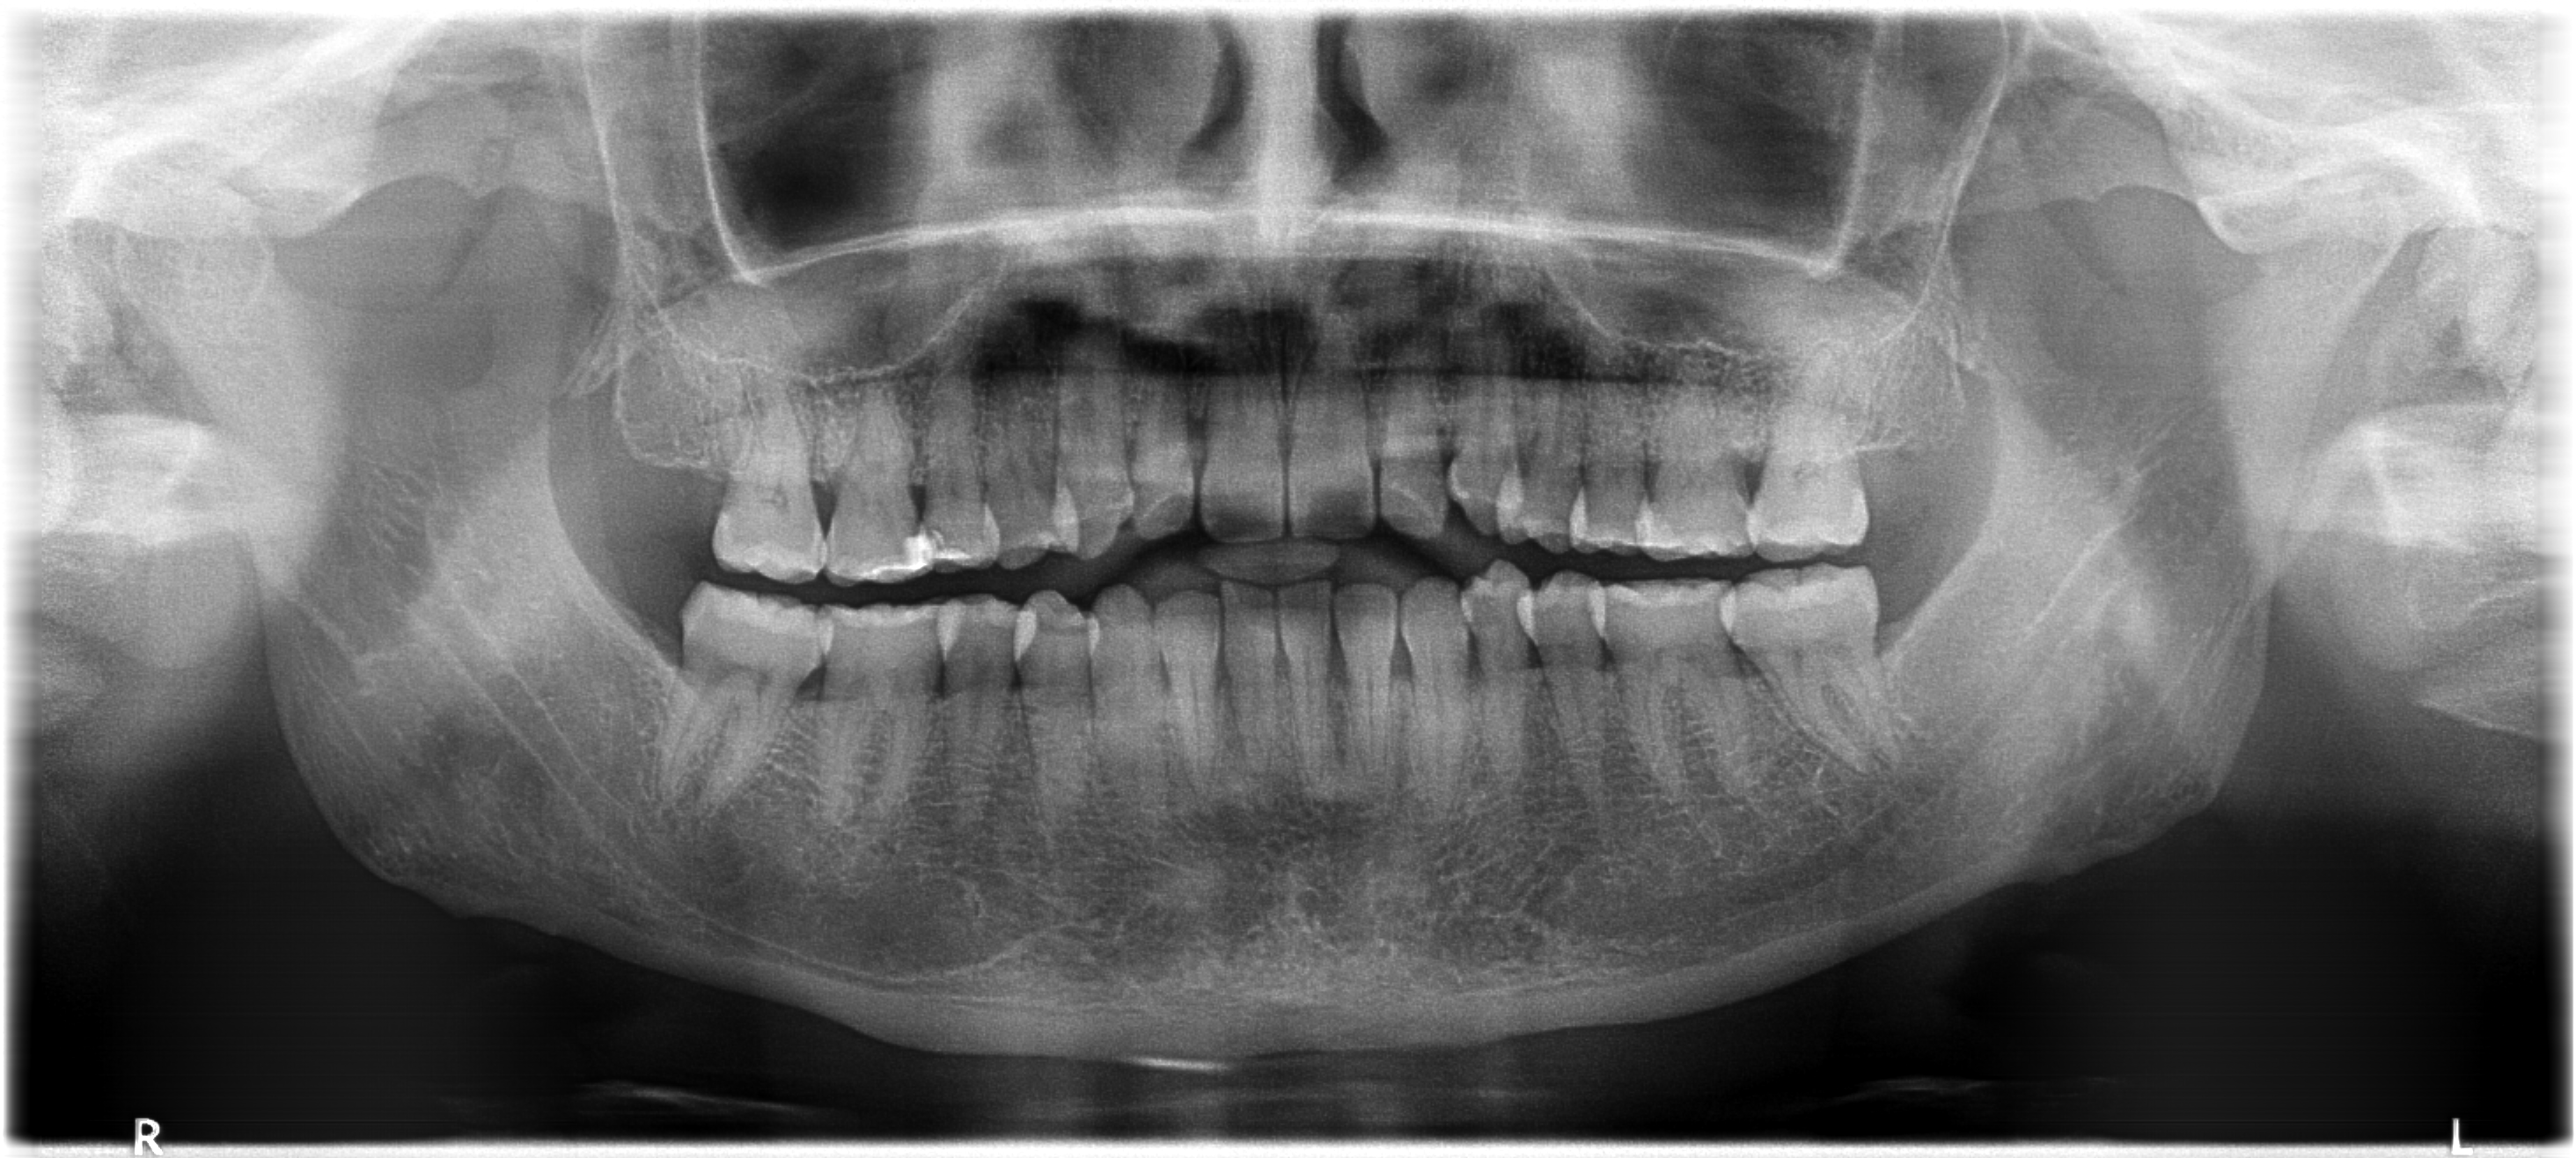

Ou escolha uma imagem de exemplo

Exemplo 2